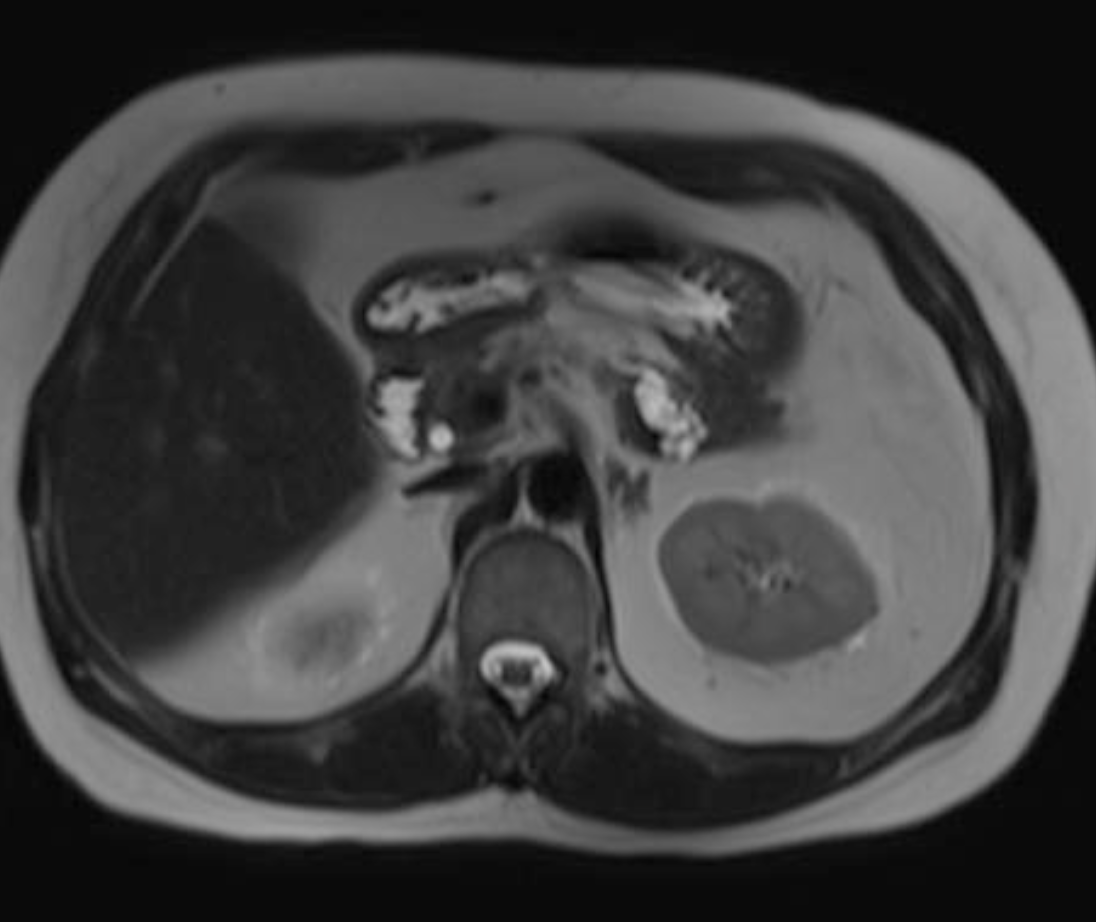

Findings: A well-defined rounded exophytic cystic lesion measuring 6.3 x 7 x 7 cm is seen originating from the tail of the pancreas. It has an average density of 8 HU and shows mild peripheral enhancement on post contrast study. A few thin septations and a tiny mural calcification are seen in it. No solid component is seen in it. Morphology of the remaining pancreas is unremarkable.

Impression: Well-defined rounded exophytic cystic lesion originating from the tail of the pancreas, which is likely, a mucinous cystadenoma of the pancreas (mucinous cystic neoplasm of the pancreas) with possible differential diagnosis of pancreatic pseudocyst (if there is a past history of pancreatitis). Another possible differential can be a hydatid cyst which is however, very unlikely.